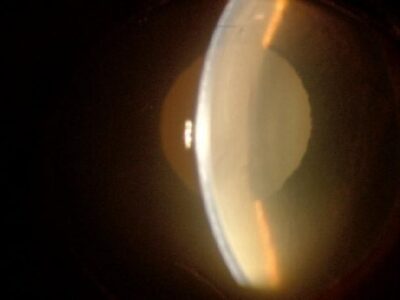

角膜内皮障害

角膜半分の領域が白濁(チワワ)

角膜の内皮が変性を起こすと実質の水分過剰によって角膜が混濁(角膜浮腫)をおこします。老齢動物や犬種による素因(ボストンテリア、チワワ、プードルなど)で見られます。難治性で進行すると角膜全体が白くなり視覚が低下します。